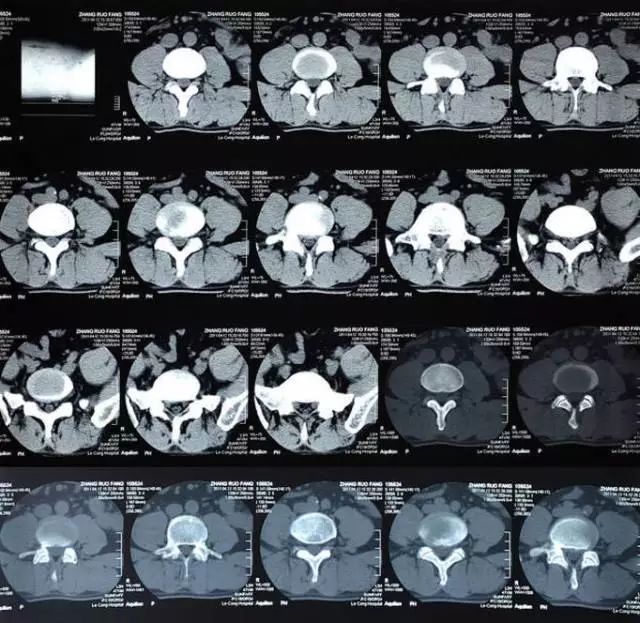

CT也是用射线穿透身体,但跟X线检查不同,现在多排螺旋CT检查是通过采集扫描范围内人体的每一个体素进行成像,说白了就是把要检查的部位划分无数体积不足一个立方毫米的微小方块,看得更细,很细微的病变也能被发现。

CT最常用在头部、胸部、腹部和脊柱疾病等方面的检查,有些四肢和骨骼问题用X线检查看不清楚时,也可以选择做CT。目前体检项目中的CT主要是胸部CT,用于早期肺癌筛查。